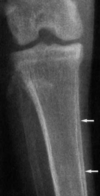

What is shown in these radiographs?

progression of generalized osteopenia after disuse

Which radiograph is normal vs. abnormal? Why?

Top: abnormal; generalized osteopenia; relative increase in opacity of vertebral endplates Bottom: normal

What is shown at the arrows in this radiograph?

double cortical line associated with generalized osteopenia